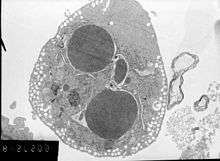

In order to perform analysis of apoptotic versus necrotic (necroptotic) cells, one can do analysis of morphology by time-lapse microscopy, flow fluorocytometry, and transmission electron microscopy. There are also various biochemical techniques for analysis of cell surface markers (phosphatidylserine exposure versus cell permeability by flow fluorocytometry), cellular markers such as DNA fragmentation[53] (flow fluorocytometry), caspase activation, Bid cleavage, and cytochrome c release (Western blotting). It is important to know how primary and secondary necrotic cells can be distinguished by analysis of supernatant for caspases, HMGB1, and release of cytokeratin 18. However, no distinct surface or biochemical markers of necrotic cell death have been identified yet, and only negative markers are available. These include absence of apoptotic markers (caspase activation, cytochrome c release, and oligonucleosomal DNA fragmentation) and differential kinetics of cell death markers (phosphatidylserine exposure and cell membrane permeabilization). A selection of techniques that can be used to distinguish apoptosis from necroptotic cells could be found in these references.[54][55][56]